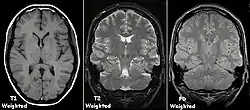

T1 e T2

Cada tecido retorna ao seu estado de equilíbrio após a excitação pelos processos independentes de T1 (spin-tretice) e T2 (spin-spin) de relaxamento. Para criar uma imagem ponderada em T1, a magnetização pode ser recuperada antes de medir o sinal MR, alterando o tempo de repetição (TR). Esta ponderação de imagem é útil para avaliar o córtex cerebral, identificando tecido adiposo, caracterizando lesões focais e, em geral, para obter informações morfológicas, bem como para imagens pós-contraste. Para criar uma imagem ponderada em T2, a magnetização pode decair antes de medir o sinal MR alterando o tempo de eco (TE). Esta ponderação de imagem é útil para detectar edema e inflamação, revelando lesões de substância branca e avaliando a anatomia zonal na próstata e no útero.

A exibição padrão de imagens de MRI é representar características de fluido em imagens em preto e branco, onde diferentes tecidos são os seguintes:

| Sinal | T1-ponderado | T2-ponderado |

|---|---|---|

| Alto | ||

| Intermediário | Matéria cinzenta mais escura que matéria branca | Matéria branca mais escura do que a matéria cinzenta |

| Baixo |